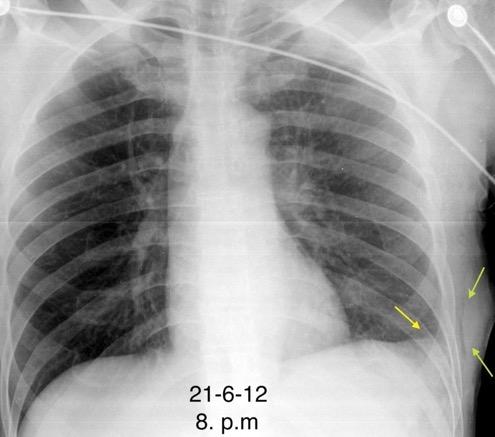

Recibe una puñalada en costado izquierdo

La laceración tiende a ocurrir en la unión

músculotendinosa . (64-90% en el lado izquierdo)

Diafragma “colgante” (“dangling sign”)

(“Dangling sign”)

TC. Mejor con multicorte. (reconstrucciones).

Asociación: Aire en pared.

Fracturas costal .Rotura esplénica. Neumoperitoneo.

Diafragma discontinúo Herniación de la grasa omental

Desser TS et al.The dangling diaphragm sign: sensitivity and comparison with existing CT signs of blunt traumatic diaphragmatic rupture. Emerg Radiol 2010